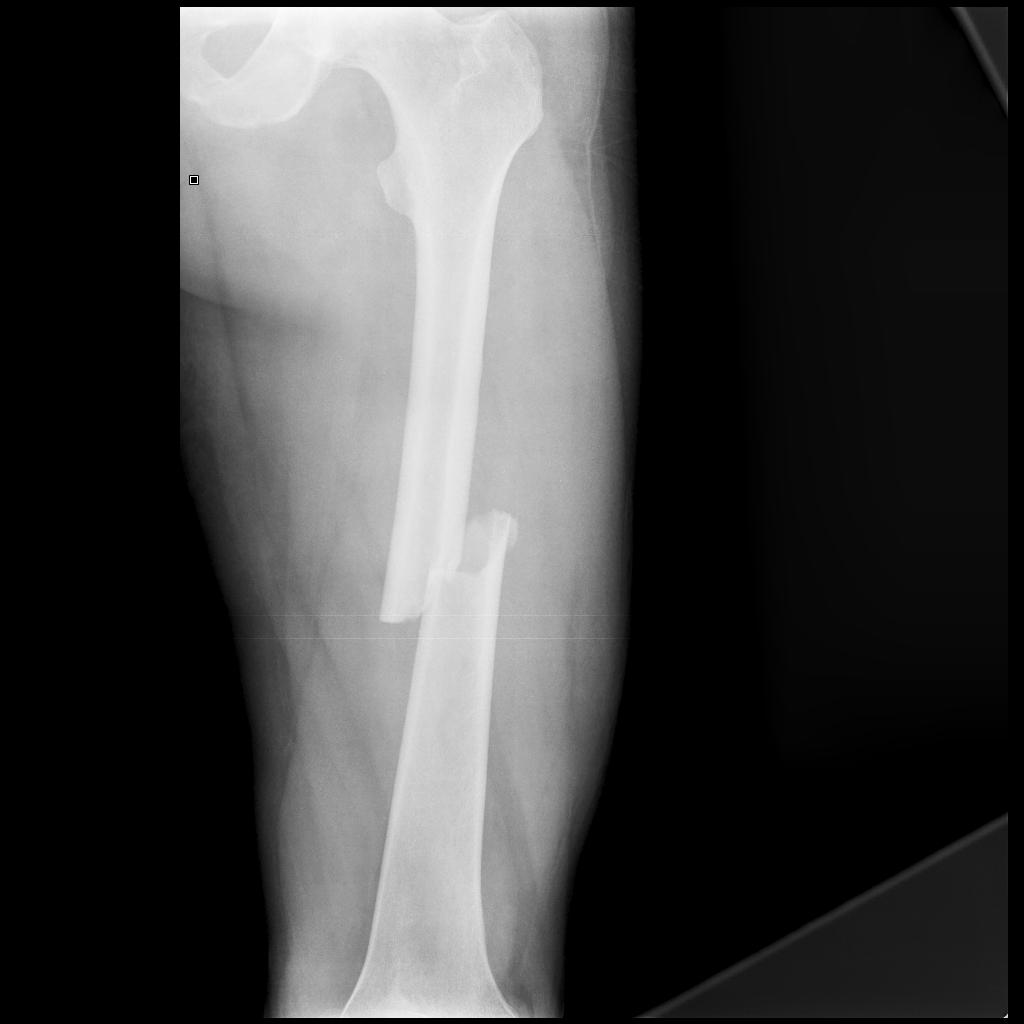

Femoral Shaft Fractures Core EM Fracture On X Ray Check the who, what, why,. They are in pain and have a reduced range. A periosteal reaction is the formation of new bone in response to injury or other stimuli of the periosteum surrounding the bone. the fracture hematoma initiates the healing response. trace around the outline of each bone as any step in the cortex may indicate. Fracture On X Ray.

Xray fracture leg stock image. Image of body, medical 123039597 Fracture On X Ray the fracture hematoma initiates the healing response. Transverse, oblique and spiral fractures. They are in pain and have a reduced range. Infection and tumours (primary and secondary) are the commonest causes of bony destruction. Within 48 hours, chemotactic signaling mechanisms attract the inflammatory cells. Check the who, what, why,. trace around the outline of each bone as any. Fracture On X Ray.